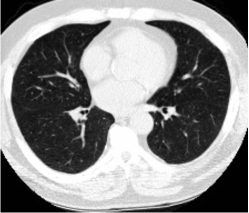

Figure 6 shows examples of the features extracted from T2-weighted and T1-weighted images prior to the feature matching step. Although the two images have different contrasts, the use of mutual information loss facilitates the learning of features that can be matched through inner product computation within the feature matching step. However, a visual comparison of the corresponding features from the two modalities reveals a lack of high visual similarity. We attribute this observation to two primary factors. Firstly, our feature matching is localized, focusing on the highest similarity within small, defined areas and not enforcing global similarity across the entire image. Secondly and more critically, the inner product computation is sensitive to both the direction and magnitude of the feature vectors. Consequently, features deemed similar by the inner product may appear visually dissimilar due to variations in magnitude. To verify this, we replaced the inner product with cosine similarity, which omits magnitude in the computation of similarity. As illustrated in Fig. 6, using cosine similarity results in features that demonstrate substantially greater visual similarity. In terms of performance, no noticeable difference in accuracy was observed; however, it is important to note that cosine similarity requires a slight increase in GPU memory usage.

| Inner Product |

![]() |

| Cosine Similarity |